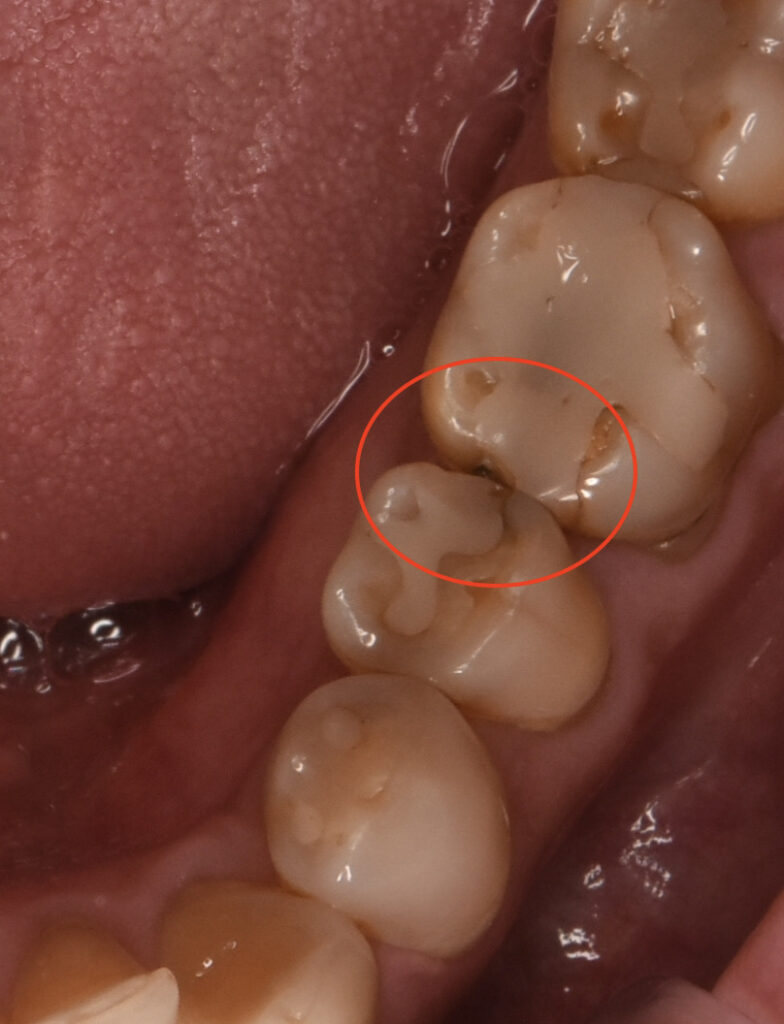

レントゲンの赤丸の部分がむし歯。

むし歯を取り除いていくと こんな感じになっていました。